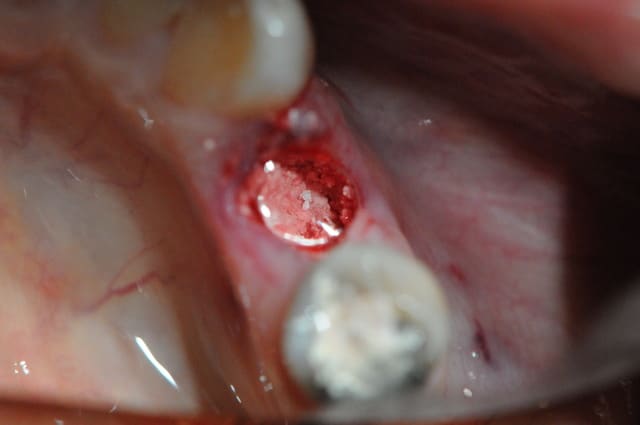

Je viens de faire l'extraction ce matin.

Je rage de ne pas l'avoir fait encore plus tôt car c'est bien ce que je craignais, toute la table externe a été bouffée par l'infection...

J'ai cureté très soigneusement et irrigué puis mis matériaux de comblement pour limiter l'effondrement en vestibulaire.

Le Bio matériau est du RTR de chez Septodont sous forme de cône pour être inséré dans les alvéoles toutes fraîches.